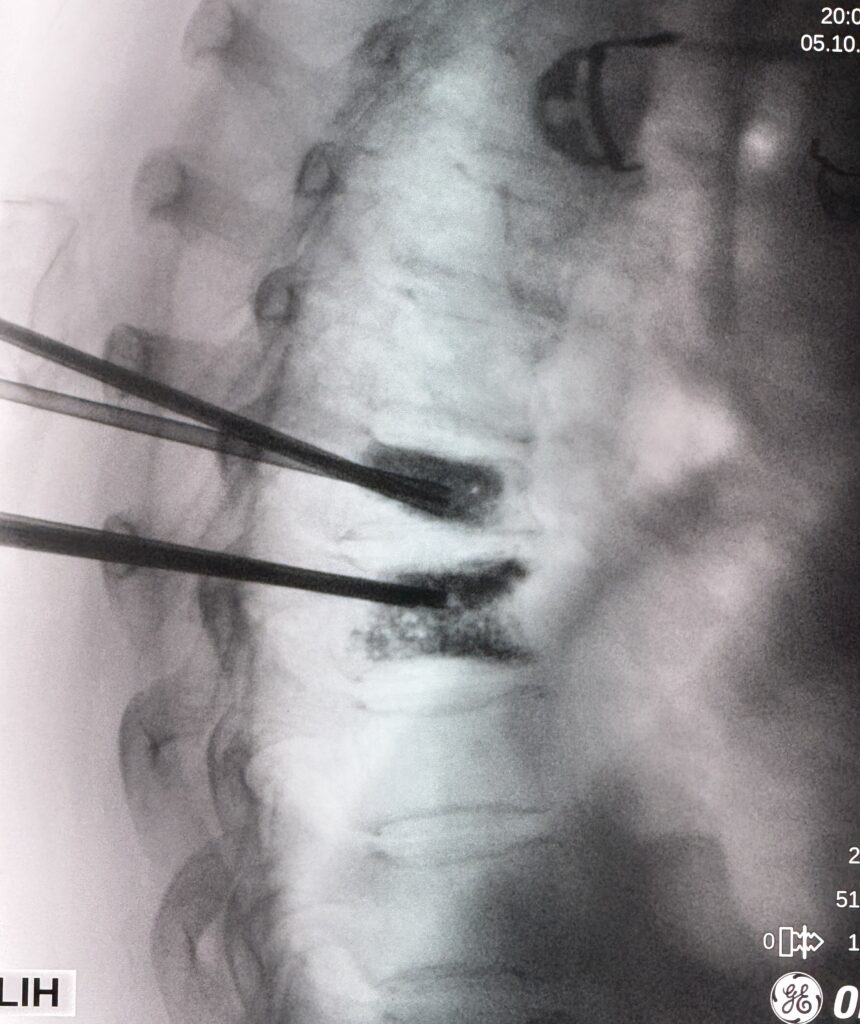

Nuestro objetivo es mejorar tu calidad de vida y acompañarte en cada paso con tratamientos mínimamente invasivos

Anestesiólogo con Subespecialidad en Algología Intervencionista con más de 10 años de experiencia en el tratamiento y alivio del dolor. Su enfoque combina profesionalismo, tecnología de vanguardia y un equipo multidisciplinario altamente capacitado para brindar atención excepcional e integral a cada paciente, mejorando su calidad de vida.